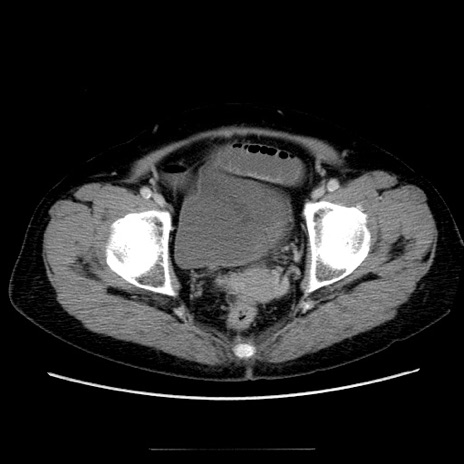

症例5(横断像)

【症例】70歳代女性

【主訴】お腹が張る

【現病歴】1週間くらい前から腹部膨満の自覚あり。昨日夜から増悪したため、本日救急外来受診。

【身体所見】意識清明、BT 36.5℃、BP 165/106mmHg、HR 80bpm、SpO2 98%、腹部:膨満、軟、自発痛・圧痛なし、触診にて不快感あり、腸蠕動音:減弱

【データ】WBC 12600、CRP 1.04